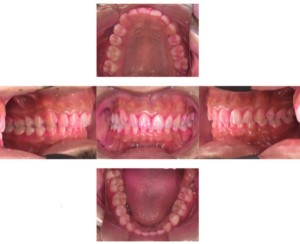

症例2

Before

症例

after

歯周病検査(治療前)

歯周病検査(治療後)

レントゲン写真

基本情報

年齢・性別 41歳・男性

主訴 主訴:歯ぐきから出血する

治療部位:全顎

治療内容 1.歯周ポケット検査、資料取り(レントゲン写真14枚・口腔内写真)、歯磨き指導

2.歯磨き指導チェック、縁上の歯石除去

3.縁下の歯石除去4回

4.再評価(歯周ポケット検査・レントゲン写真14枚・口腔内写真)

5.メインテナンス

治療期間 1日

治療費 合計:14,160円

内訳(全て保険診療3割負担)

・初診検査、歯磨き指導、縁上の歯石除去:3,630円

・レントゲン写真、縁下の歯石除去①:3,040円

・縁下の歯石除去②:1,530円

・歯磨き指導チェック、縁下の歯石除去③:2,070円

・縁下の歯石除去④:1,530円

・再評価:2,360円

(2022年5月現在現在)

リスク・副作用 ・歯石除去後すぐは歯ぐきを触っているため歯ぐきに違和感や痛みを感じる場合がある

・歯石除去により今まで腫れていた歯ぐきが引き締まり歯ぐきが下がる可能性がある

・歯ぐきが引き締まって下がることにより歯面が今までより露出し知覚過敏の症状がでる可能性がある

・歯石除去後、歯磨きを怠ると細菌が歯周ポケットのより深部まで入ってしまうため歯周病が悪化してしまう可能性がある

・一度歯周病になると再発しやすい為、定期的なメインテナンスが必要になります

治療方針 1.歯磨き指導

2.歯ぐき上の歯石除去

3.歯ぐき下の歯石除去

4.再評価

5.定期的なメインテナンス

特記事項 ・着色除去(PMTC)は自費治療のため希望しませんでした。

・右下7番の歯周ポケット5mmは親知らずの関係もあり、このまま維持していくことを説明しています。

・他4mmの歯周ポケットに関しては歯垢が少し残っていた為、再度歯磨き指導と、縁下の歯石を確認して様子をみることにしました。

担当者所見 全体的に出血が見られたのと、奥の歯ぐきは炎症があり歯周ポケットが深かった為、まずは歯ブラシの当て方+歯間ブラシ3Sサイズを使用して頂き炎症を落ち着かせました。

両方毎日使用して頂いた為、スムーズに歯周病治療を行うことができました。毎日のホームケアが不十分だと、なかなか結果に繋がらず、治療期間も長くかかってしまう為、患者様の協力が歯周病治療を成功させるためにはかなり重要になっていきます。

そして一度病気になった歯ぐきは再発しやすい為、今後は3ヶ月に1度の定期的なメインテナンスで、この状態を維持できるよう一緒に管理していきます。